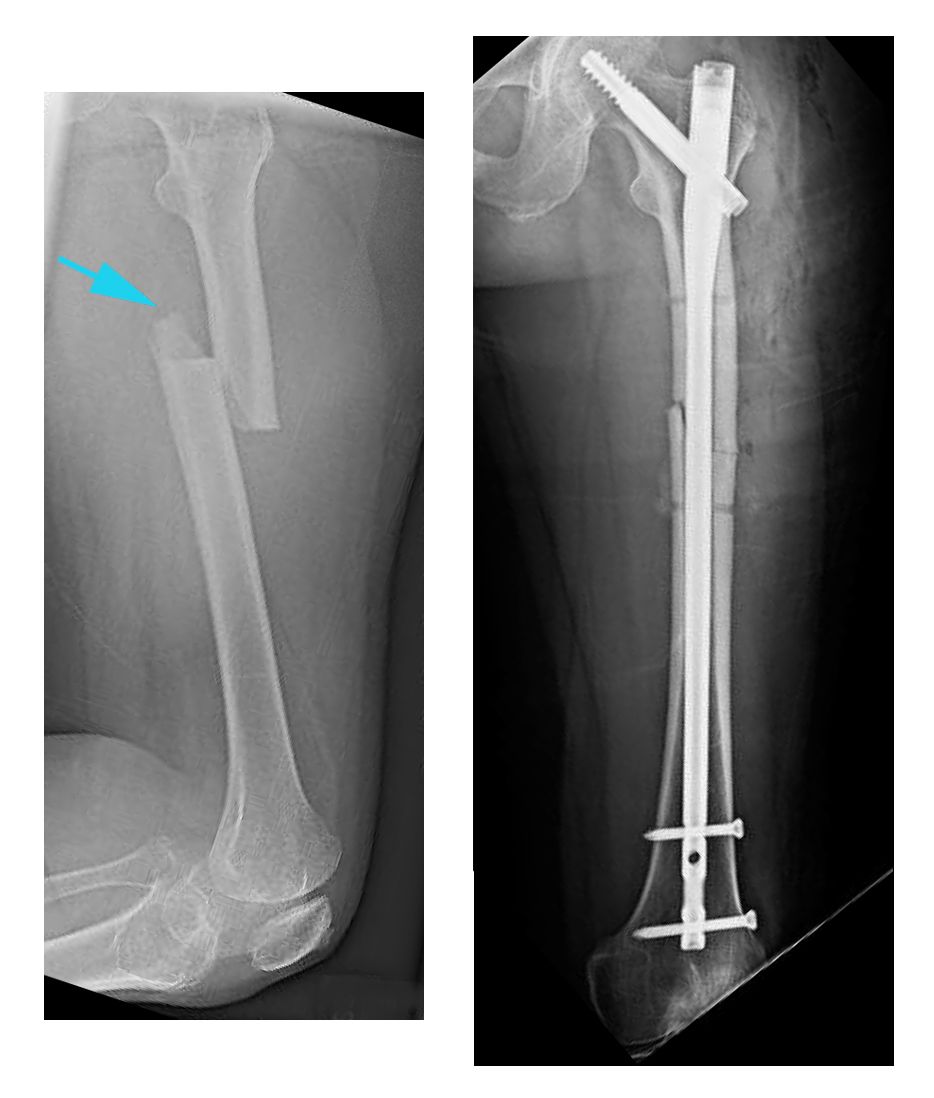

Returning to Work After a Femur Fracture- AutoAccident.comIntroductionPhysical therapy in Conway for Hip IssuesWelcome to the FYZICAL Conway Guide for Fractures of Femur Adults. Welcome to the Conway FYZICAL Guide for Fractures of Femur Adults. The thigh bone, or the femur is the longest and strongest bone in the body. It takes a lot of strength to break the femur in an adult so it is often accompanied by other injuries. Fracture is a disability problem, severely limiting mobility until it stabilizes. Until recently the most common way to treat a fractured femur was to apply traction, the source of a thousand cartoons and jokes. Fortunately, modern treatment usually stabilizes the bone fairly early and allows to move on crutches. This guide will help you understand: Anatomy What structures are most commonly injured? The femur extends from the hip to the knee and represents a quarter of the average adult height. You can feel the lower end of the femur on the knee. The upper end is deeply buried in the hip muscles, but you can feel the boní top of the greater trochanter on the outer side of the hip. The bone shaft is a hollow tube with strong dense compact bone on the outside and fatty tissue without structural force inside. The shaft breaks when the impact, bending, torsion or compression emphasizes the bone. Causes How do femur fractures occur commonly? Fractures of the femur axis occur in high-energy traumas, such as motor vehicle accidents and height drops. The injuries caused by gunshots and explosions also cause severe open fractures in this area. Lower energy accidents that can cause a thigh bone fracture include collisions in sports, ski injuries and twisted injuries. TypesImpact against the thigh causes a bending force that compresses one side of the bone and stretches the other. This may result in a short oblique fracture or a three-part fracture with a short triangular fragment. A twisted force can be applied to the thigh bone when the foot or lower leg is trapped and the weight of the upper body is turning. This causes a spiral fracture of the bone. The compression along the bone line causes a transverse fracture. This can happen in a car accident when the knee hits the dashboard and the force is transmitted to the bone. Bone injury is only a part of the total image when a fracture occurs. Muscle injuries, tendons, ligaments, skin, blood vessels and nerves can be more important than broken bone. This is particularly true in femur fractures. The strength needed to break the thigh bone often causes much damage to the other structures in the thigh. An open fracture in which the bone leaves through the skin is a particularly serious problem. SymptomsWhat symptoms cause femur fractures? The main immediate symptom of the injury is pain in the thigh and inability to use the leg. It's very rare for someone to walk on a broken thigh bone and not be tried. The leg is often unstable and does not move like one. Usually, the broken leg will be shorter than the other and distorted. There will be inflammation and tenderness at the fracture site. There may be loss of feeling and movement of the foot if the nerve or blood supply has been affected. If the bone has passed through the skin, the wound will be obvious. Internal bleeding from a broken femur can be significant by causing a rapid heart rate and low blood pressure leading to shock. Pain will remain significant for several weeks as the thigh bone is healed, but this will be reduced if the bone stabilizes by surgical fixation. Swelling, tenderness and mass bruising are also symptoms that often last weeks. Evaluation How will my fracture be evaluated? The first-aid evaluation at the accident scene will include questions about the nature of the accident, place of pain and ability to move the leg. The patient's state of shock will also be evaluated. The leg will be evaluated for wounds, sensation and blood supply. The leg will usually have to be sculpted before being transported to the hospital. The patient should stay warm and still. In the emergency room patients will be more evaluated for shock and blood loss, as this can be significant. The patient will be carefully examined by other injuries, especially in the case of a high energy accident with its potential to cause multiple traumas. The vascular and nervous supply of the limb will be carefully checked. The extremity will stabilize with sprinkles, sandbags or skin traction. Careful leg palpation, paying attention to the knee and bed, as well as thigh and hip, can give an indication of other injuries. Routine tests are performed to evaluate the loss of blood and the general biochemistry of the body before anesthesia. The thigh X-rays are a vital part of the evaluation of this injury. TC or RM scan is usually not necessary for these fractures. The standard X-ray views are an anteroposterior view (AP) of the entire thigh bone from the hip to the knee and a side axis view. It is very important to obtain satisfactory X-rays of the hip and knee joint to ensure that these regions are not also fractured. Even with good X-rays a small number of hip fractures are not discovered in the initial evaluation. Treatment What treatments should I consider? Surgery A few years ago this type of fracture was treated more commonly in traction. However, in North America most patients with a broken thigh bone are now treated by surgery. This surgery consists of straightening (reducing) fracture and stabilizing it with a stick of past metal inside the bone and fixed to the bone at the top and bottom to avoid shortening and rotation. Traction can be recommended in some cases where the risks of a more important operation seem too large. A metal pin is passed through the bone either above or just below the knee. The slangs and thinnings support the leg, and 15-25 pounds or 7-11kg weights are glued by the ropes and pulleys to the pin. The principle behind the use of the traction is that pulling the bone so straight and keeping it still. Traction should be maintained until the healing process is advanced to the point where the fracture does not move when the traction is removed. This usually takes six to eight weeks in an adult. After this traction period the fracture must be protected in a body mould, otherwise it is susceptible to shortening, angular or rotating. The molten body, from the chest to the ankle is maintained for a few months until the fracture is joined. If the fracture has a very stable pattern, it may be possible to treat it in a cast brake after the initial traction period. Apart from the significant prolonged rest inconvenience for traction, prolonged immobilization and a body caste, this way of treating the fracture was found causing a number of problems such as malunion, no union, stiffness, weakness and poor functional recovery of the injury. Thus, the reason for treating a fractured femur is because the results of non-operative treatment are not consistently good. Surgery is performed under general or spinal anesthesia. The bone is straightened and kept straight by traction. Then a small hole is made at the top of the thigh bone and a thin wire is passed into the bone, crossing the fracture and entering the lower fragment. The inside of the bone can be rememorated (cleaned) to ensure a tight fit. Then you pass an Intramedular Rod (the IM Rod or the IM Nail) on the guide wire inside the femur and is secured with screws at any end. With some fracture patterns or with open fractures, an external fixing device can be used. To apply an external fixer, the bone is straightened and the large threaded pins are passed in the bone fragments above and below the fracture. These pins join a rigid frame outside the thigh, which keeps the fragments in position while the healing process takes place. When the fracture extends a lot along the axis to the knee, a plate can be used. The greatest advantage of the operational treatment of a fractured femur is that it allows the patient's freedom to move, walk on crutches very soon after surgery and leave the hospital early. The bone is not cured by surgery, but it still remains to improve the healing possibilities. The fastest recovery of normal hip and knee movement prevents future problems of stiffness and weakness. Implants are removed often after the bone is healed. External fixers are always eliminated. Plates are also removed quite often as they can give the patient some symptoms and can often be felt through the skin. Removing IM rods is done only when they cause symptoms. The removal operation is relatively simple and recovery is usually quite fast (six weeks) however, the bone may need some time to recover the full force after the hardware has been removed. When there are no symptoms attributed to it, the removal of the hardware is controversial. Some surgeons defend it because the presence of a plate or a rod can weaken the long bone term; others leave the hardware and point to the small but significant incidence of refracture in the three months after the implant is removed. Rehabilitation What happens when I recovered from surgery? The normal process without complications of bone healing takes six weeks to get 50% of the eventual bone force, three months to reach 80% of bone strength and the consolidation and remodeling of the fracture site can continue for 18 months. The consequences of this timetable are that the fracture needs protection during the first three months. The first time in this means using crutches and not putting much weight through the injured leg otherwise the fixing will fail. To determine when more weight can be placed through the thigh, the orthopaedic surgeon will supervise the healing with x-rays at intervals. When the new bone formation (callus) is evident that it passes through the fracture, it can be encouraged to put more weight on the leg. Although the actual bone healing can be 50 or 80%, the overall recovery of fracture and surgery also requires proper muscle strength and resistance, as well as a range of movement and joint control. Physical therapy at Conway FYZICAL can help you achieve this. Rehabilitation at FYZICAL Conway will begin as soon as your surgeon recommends it. Sometimes therapy is recommended even before you are allowed to completely weight the bear. In other cases, rehabilitation will not be recommended until full or almost complete weight begins. Each surgeon will establish its own specific restrictions based on the type of fracture, surgical procedure used, personal experience, and if the fracture is cured as expected. Even if it is physical The therapy for the injured leg has not yet begun, in FYZICAL Conway we recommend keeping the rest of the fitness of your body with regular exercise. You can use a superior bike if you are a non-weight bearing or you can even be advised to do non-peso bearing exercises in a pool. A stationary bike is often the best cardiovascular activity once the weight bearing starts. Weights for upper limbs and other legs are also strongly encouraged. Your physical therapist at FYZICAL Conway can provide a program for you to keep your overall physical condition while recovering from your surgery. If you are still wearing crutches for the moment we see it for the first time in FYZICAL Conway, your physical therapist will ensure that you are using them safely, properly and safely and that you are respecting for your weight restrictions. We will also make sure that you can safely use your crutches on the stairs. If you are no longer wearing crutches, or once you no longer need them, your physical therapist will focus on re-education of the normal gait. Until you can walk without a significant limp, we recommend that you continue to use your crutches, or at least a miga or a rod/camine. Inappropriate bitness can lead to a multitude of other pains on the knee, hip, and back, so it is prudent to use a walking help until you can reach a normal walk. Your conway physiotherapist FYZICAL will advise you on the appropriate time for you to be walking without any help to walk. Patients may experience pain when they begin to put weight through their leg. This pain may be from not using joints and muscles regularly or may be of concurrent injury to the soft tissue that occurred when the thigh is broken. During your first appointments at FYZICAL Conway your physical therapist will focus on relieving your pain. We can use modalities such as heat, ice, ultrasound or electrical current to help decrease any pain or swelling that has around the surgical site or anywhere by the extremity. In addition, your physical therapist can massage your leg and ankle to improve circulation and help decrease pain. The next part of our treatment will focus on recovering the range of movement and strength across its bottom. Your limb will be seen and will feel quite weak after you do not use it for a prolonged period. Your physical therapist at FYZICAL Conway will prescribe a series of stretching and strengthening exercises that you will practice at the clinic and also learn to do as part of your home exercise program. We will focus especially on winning range of motion on the knee as the knee can become rigid easily if the early movement is not encouraged. As for strength we will focus on the muscles of your hip and thigh, but you can even give exercises for areas such as your ankle or back as these areas help support the lower limb when you are bearing weight. An electric muscle stimulator can be used to help your muscles in hiring while doing your exercises, which will help you gain your strength back faster. Exercises may also include stationary cycling and the use of Theraband or weights to provide some resistance to your lower leg. If necessary, your physical therapist will mobilize your joints. This practical technique encourages rigid joints of the hip, knee, ankle and foot to gradually move in their normal range of motion. The mobilization of joints can be combined with the assisted stretching of any muscle tightened around the surgical site. Fortunately, the initial stages of winning range of movement and strength after a femur fracture goes quickly. You will notice improvements in the functioning of your entire leg even after a few treatments with your physical therapist at the Conway FYZICAL. As your range of movement and strength improves, we will advance your exercises to ensure that your rehabilitation is progressing as quickly as your body allows. As a result of any injury, receptors in their joints and ligaments that help with balance and proprioception (the ability to know where your body is without looking at it) decrease in function. A period of immobility and weight reduction will add to this decrease. If your balance and proprioception has decreased, your joints and your member as a whole will not be as efficient as they function and the decline can also contribute to a potential injury in the future. As a final component of our treatment, your physiotherapist at FYZICAL Conway will prescribe exercises to regain balance and proprioception. These exercises may include activities such as standing on a foot or balancing on an unstable surface such as a wobble board or a soft plastic disk. Advanced exercises will include agility-type exercises such as hoarding, jumping or moving side by side. Eventually we will encourage exercises that mimic the rapid movements of the sports or activities in which you enjoy participating. Once the fracture shows signs of X-ray consolidation you can use the leg more normally and return to heavier activities and sports. This stage is usually between three and 18 months after injury and depends on both muscle strength recovery and resistance and bone recovery. The fact that the healing process can continue for 18 months means that the symptoms of pain, agitation, swelling, and weakness can continue for a long time after the bone appears "heavy" on the X-ray, but it must gradually decrease and then disappear. Generally, the strength and stiffness that an experience after surgery to repair a femur fracture responds very well to the Physical Therapy that we provide in FYZICAL Conway, however, if your pain continues beyond what you should or therapy is not progressing, as your physical therapist at FYZICAL Conway would expect, we will ask you to continue with your surgeon to confirm that the surgical site is tolerating the complications well and. In general, the prognosis for the total recovery of a fractured thigh bone is encouraging. The bones of most people heal in a good position and recover almost the normal function. Most of those who do not recover the full function have had the injury or its complicated treatment by one or more of the problems discussed in the next section. FYZICAL Conway offers services for physical therapy in Conway. Abstract A fracture of the thigh bone is a serious injury with the potential for long-term serious problems. It is also commonly associated with other injuries. Modern treatment with IM rod fixing fixes the fracture in a good position and allows early mobilization, pain relief and discharge from the hospital. Complications of this type of treatment are relatively rare and it is normal to return to full activity, however full recovery may take up to 18 months. portions of this copyright document MMG, LLC